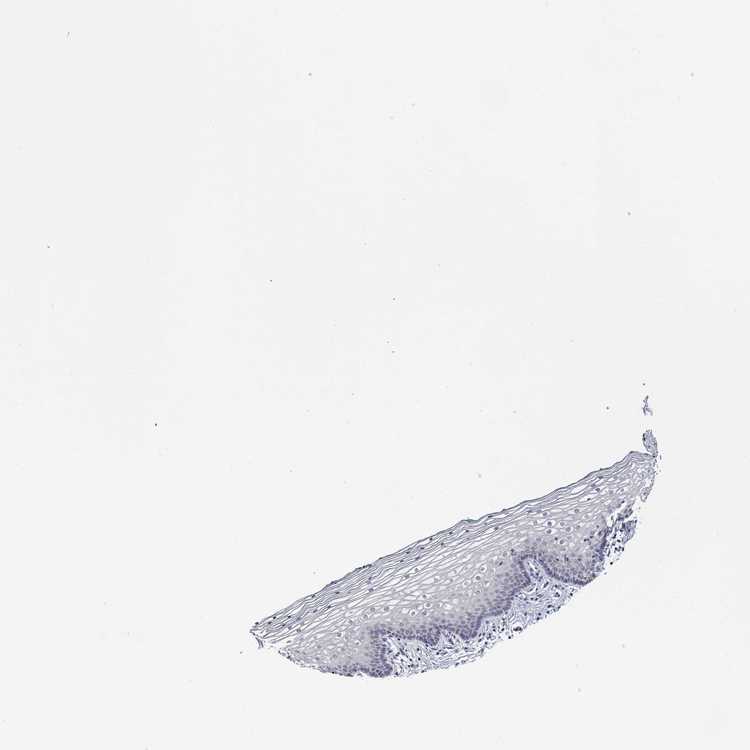

TISSUE PRIMARY DATA VAGINA Show tissue menu

VAGINA - Antibody stainingi

Antibody staining in the annotated cell types in the current human tissue is reported as not detected, low, medium, or high, based on conventional immunohistochemistry profiling in selected tissues. This score is based on the combination of the staining intensity and fraction of stained cells.

Each image is clickable and will lead to virtual microscopy that enables deeper exploration of all samples and also displays staining intensity scores, fraction scores and subcellular localization as well as patient and tissue information for each sample.

Antibody HPA014405Antibody HPA065785

Squamous epithelial cells Not detectedNot detected